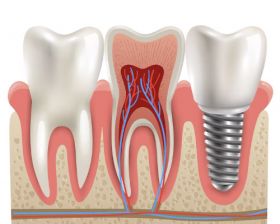

Eco Care Dental in Nizampet, Hyderabad, is a leading dental clinic that provides a full spectrum of dental services. With state-of-the-art technology and a team of experienced dentists, the clinic is dedicated to offering high-quality, patient-centric dental care. Whether you need preventive, restorative, or cosmetic dental treatments, Eco Care Dental ensures personalized treatment plans to meet your unique oral health needs.